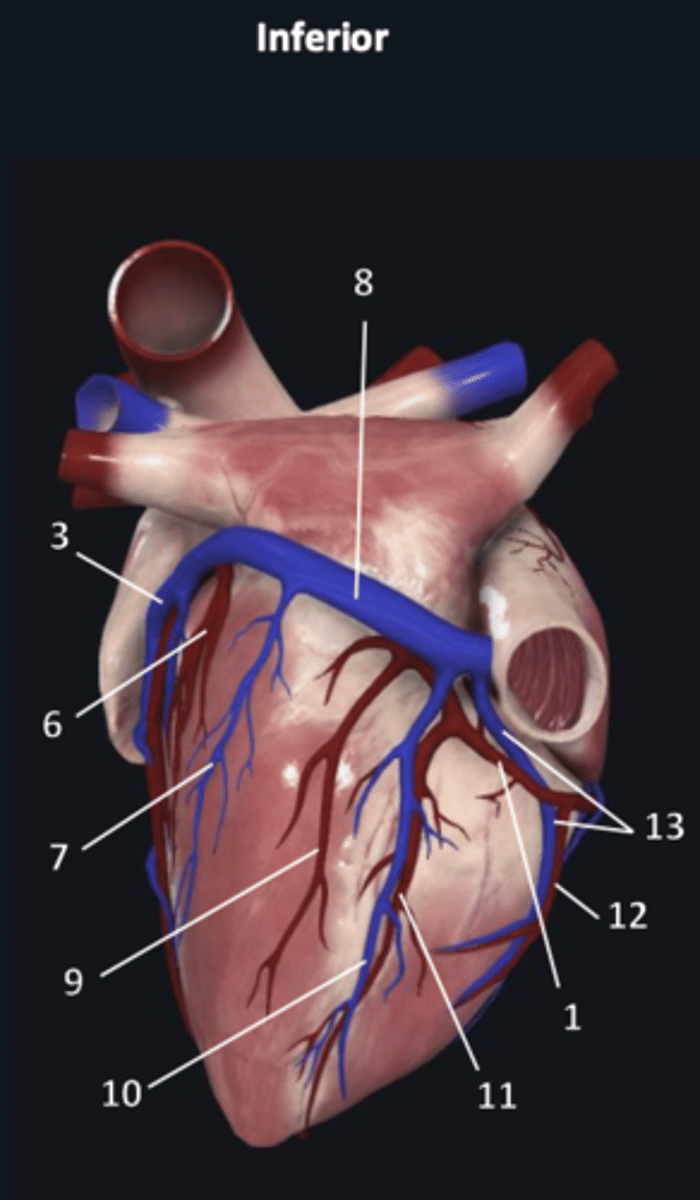

right coronary artery

1

anterior interventricular artery

2 (red)

great cardiac vein

3 (blue)

anterior interventricular artery

2 (red)

great cardiac vein

3 (blue)

left marginal artery

4

left marginal vein

5

posterior left ventricular artery

6

posterior vein of left ventricle

7

coronary sinus

8

right coronary artery

1 (red)

great cardiac vein

3

posterior left ventricular artery

6

posterior vein of left ventricle

7

coronary sinus

8

right posterolateral artery

9

middle cardiac vein

10

posterior interventricular artery

11

right marginal artery

12

small cardiac vein

13